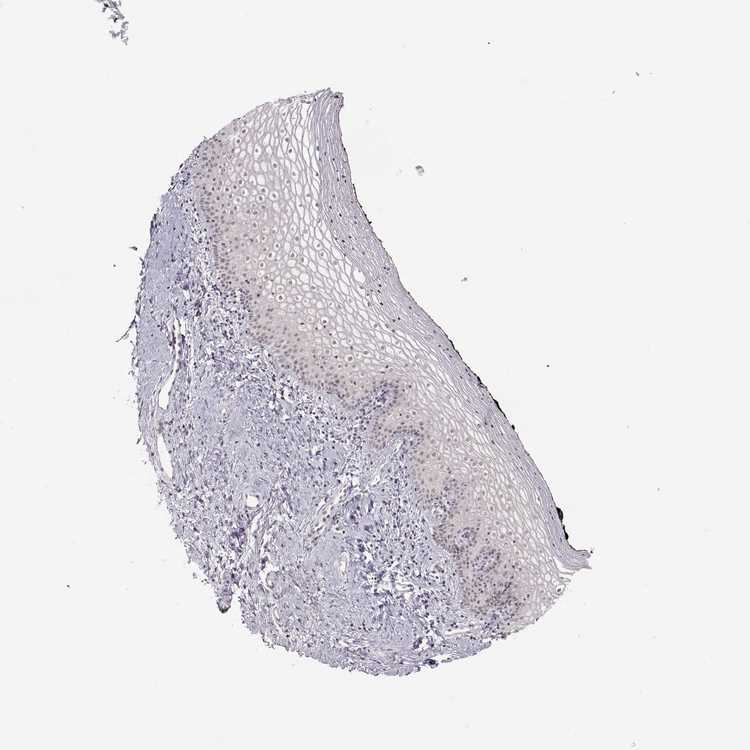

TISSUE PRIMARY DATA VAGINA Show tissue menu

VAGINA - Antibody stainingi

Antibody staining in the annotated cell types in the current human tissue is reported as not detected, low, medium, or high, based on conventional immunohistochemistry profiling in selected tissues. This score is based on the combination of the staining intensity and fraction of stained cells.

Each image is clickable and will lead to virtual microscopy that enables deeper exploration of all samples and also displays staining intensity scores, fraction scores and subcellular localization as well as patient and tissue information for each sample.

Antibody CAB020785

Squamous epithelial cells Not detected